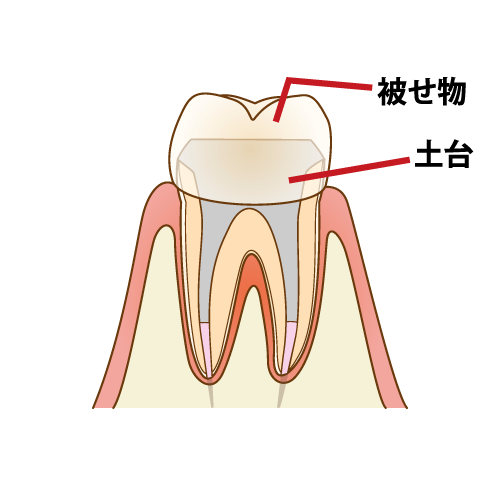

土台作り

治療を行う歯は、度重なる切削によって歯の大部分を失っているため、このまま根管内部に被せ物を装着しても、長期の安定が見込めない場合があります。

そこで、行うのが支台築造(土台の形成)です。歯質を補修したり、歯の根が折れたり割れたり(歯根破折)しにくくして再感染を防ぎます。

まだ虫歯が残っていれば一緒に削り、型取りができるように形を整えます。

被せ物の治療

根管治療を行った歯の虫歯の再発を防ぐには土台の歯と隙間なく適合する精度の高い被せ物をすることが不可欠です。土台の処置がしっかり行われていても、被せ物の精度が低ければ、健康な状態を維持する事は不可能です。耐久性の高い素材の選定をし、精密な被せ物を作製します。

作成した被せ物を装着し、噛み合わせの調整を行います。